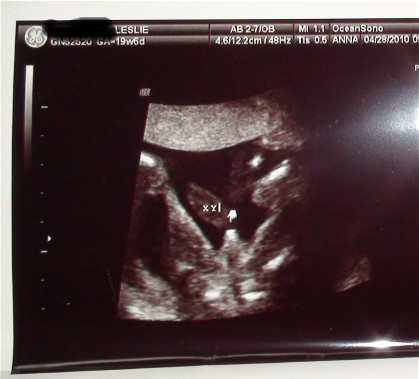

Looks like to me

This is my sono

That's a girl. I am due the week before you are and this was my "money shot" from the Level 2 which was done about 2 weeks ago:

Needless to say, I am DEFINITIVELY having a boy.